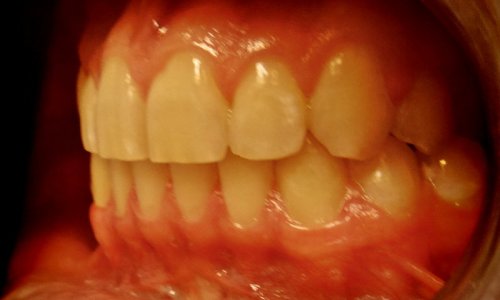

Zgryz Po

Proste Zęby

Rezultat: Leczenie przebiegało zgodnie z planem i trwało niecałe 2 lata.